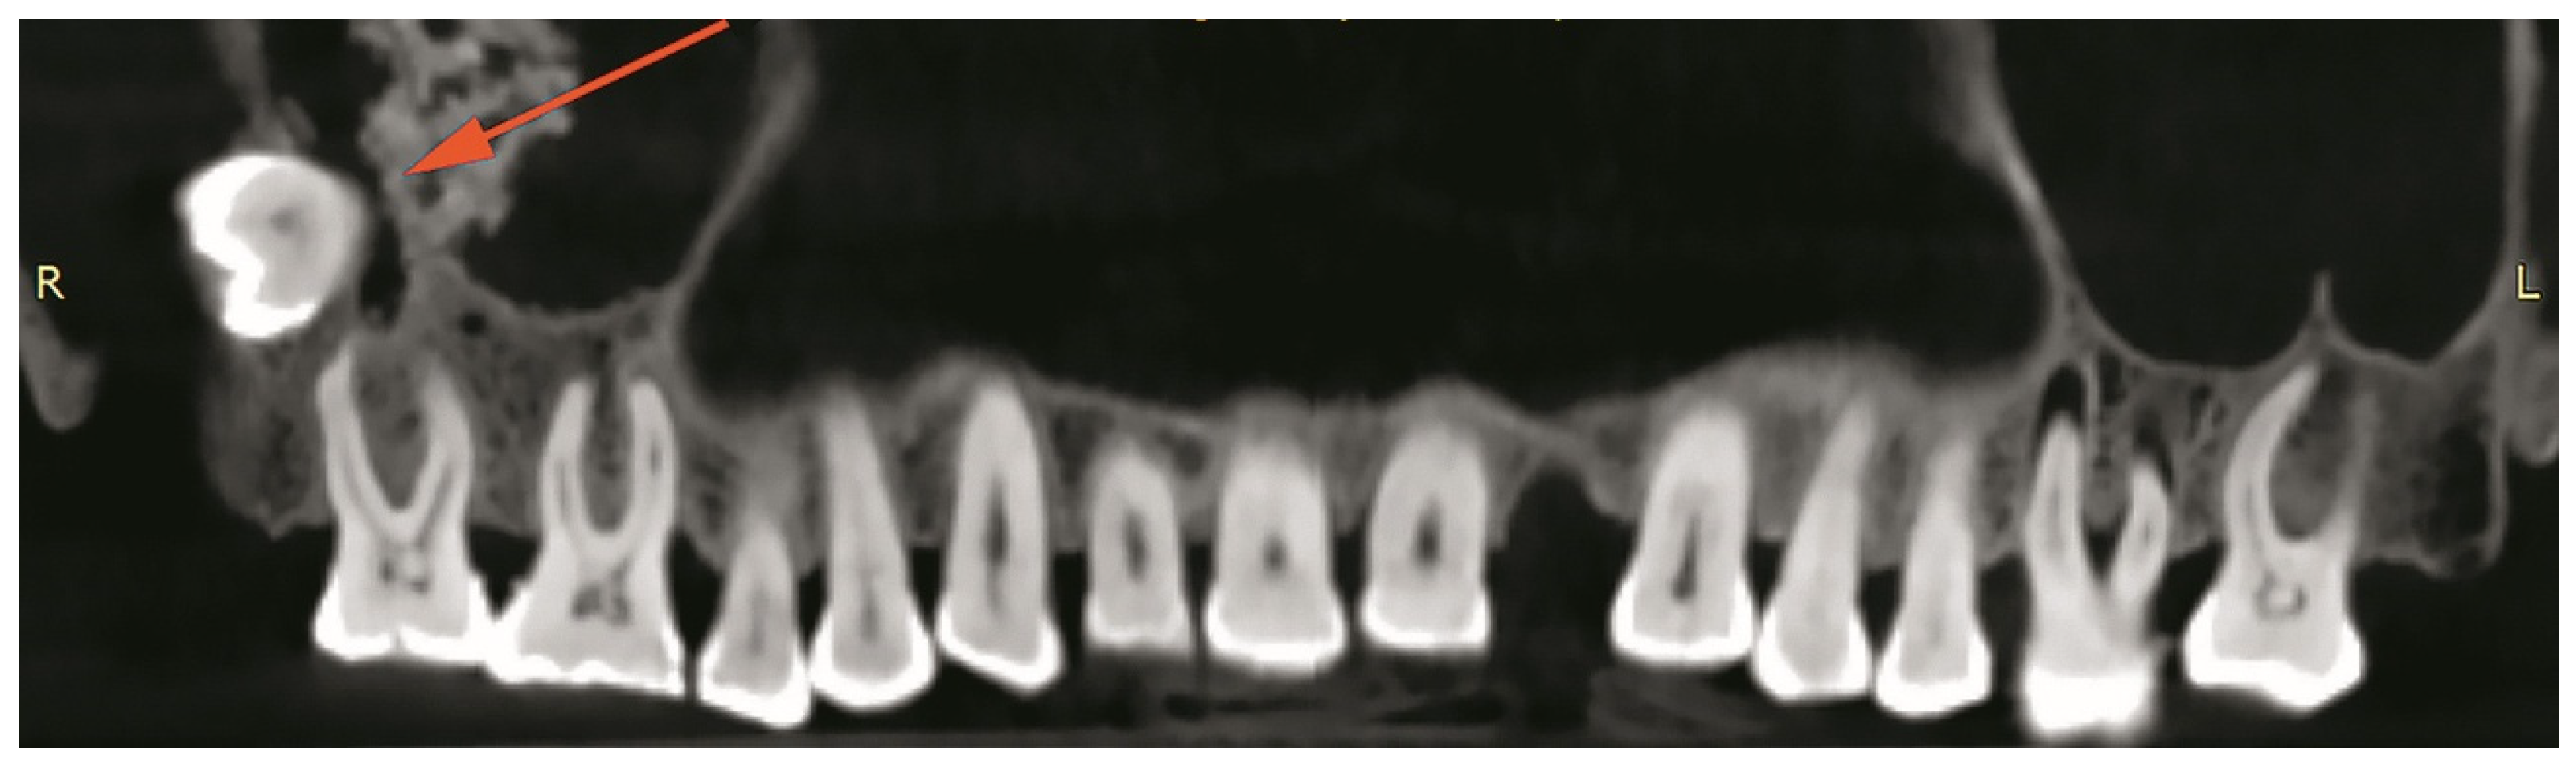

The study aims to reconstruct the life history of an individual whose skeleton was recovered during the excavation of the late medieval Pauline monastery of the Blessed Virgin Mary on Moslavina Mountain, Croatia. The monastery was one of the most important ecclesiastical centres in continental Croatia during the 14th/15th centuries CE and was abandoned between 1520 and 1544 due to fear of imminent Ottoman attacks. The inscription and coat of arms on the tombstone of a tomb located in the chancel, next to the main altar, indicate that the skeleton belongs to Sofia Kaštelančić née di Prata (di Pordenone), a member of Croatian late medieval high-ranking nobility. We conducted a conventional bioarchaeological study, carbon and nitrogen stable isotopes analysis, paleoradiological imaging (CT/CBCT scanning), and three-dimensional facial reconstruction. The skeleton belongs to a middle-aged woman between 40 and 50 years old with an estimated stature of about 161 cm. Numerous pathological changes, such as ante mortem tooth loss, caries, abscess, linear enamel hypoplasia, dysodontiasis, and osteophytosis were observed, with the most notable pathology being the fracture of the right ankle, a fact also confirmed by CT scanning. Carbon and nitrogen isotopic values are consistent with a terrestrial diet based on C3 plants with no marine input, and the consumption of large quantities of animal-based proteins. Three-dimensional facial reconstruction made it possible for the first time in over 500 years to obtain the approximate physical appearance of the individual. The presented results are consistent with the hypothesis that the skeleton probably belongs to Sofia Kaštelančić. Nevertheless, none of the observed osteological traits are individually or collectively diagnostic of Sofia, so, in the absence of individualising evidence, the identification remains hypothetical rather than demonstrative.